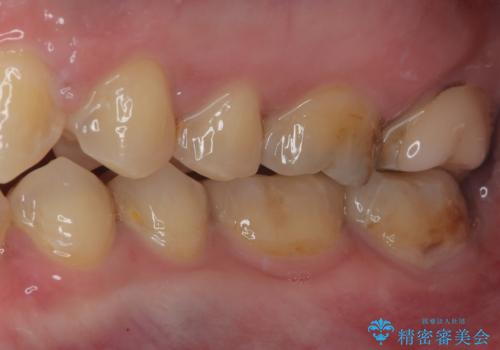

銀歯を白くしたい セラミックインレー修復

金属がなくなり大変満足していただけました。

引き続き矯正後の後戻りのチェックで来院してもらうつもりです。